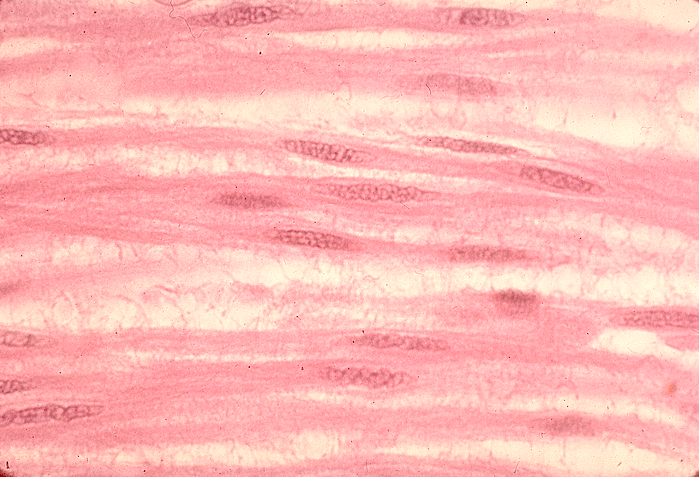

Smooth Muscle Tissue

Smooth Muscle Tissue 117 photos